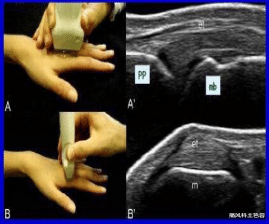

五、关节B超(肌骨超声)

肌骨超声检查主要是对关节周围软组织和关节腔里面的动态炎症的评估 , 对疾病早期的诊断、预后 。 它被誉为医生的眼睛 , 利用高分辨率的超声探头和彩色多普勒成像技术 , 对关节及其周围软组织进行检查 , 查明类风湿患者各阶段 , 尤其是早期炎症堆积部位 , 明确关节软组织的侵蚀和破坏程度 , 精准监测关节内环境 , 帮助医生快速判定病情的严重程度与发展阶段 。